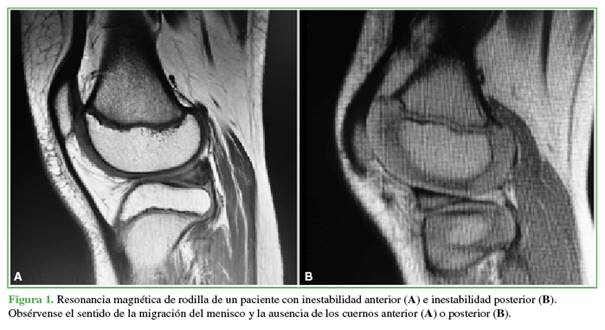

Se evalúa el patrón de desgarro del menisco discoideo con el gancho de exploración, verificando la inestabilidad periférica. Se coloca el gancho en el hiato poplíteo para traccionar el cuerno posterior hacia adelante y confirmar el grado de inestabilidad. Si se puede acceder fácilmente al sitio del desgarro, la reparación meniscal puede realizarse antes de la saucerización. De esta manera, es posible identificar, con más precisión, las áreas del menisco discoideo que deben ser resecadas. Esto ocurre habitualmente cuando hay una lesión con migración anterior o posterior del menisco (Figura 1). Cuando el acceso puede ser difícil debido a que un menisco discoideo voluminoso impide la visualización de la lesión o la ubicación de la inestabilidad periférica, se puede hacer, primero, una resección limitada cuidadosa de la región central del menisco discoideo. Esto permite una mejor visualización y acceso a la parte periférica del menisco para efectuar la reparación.